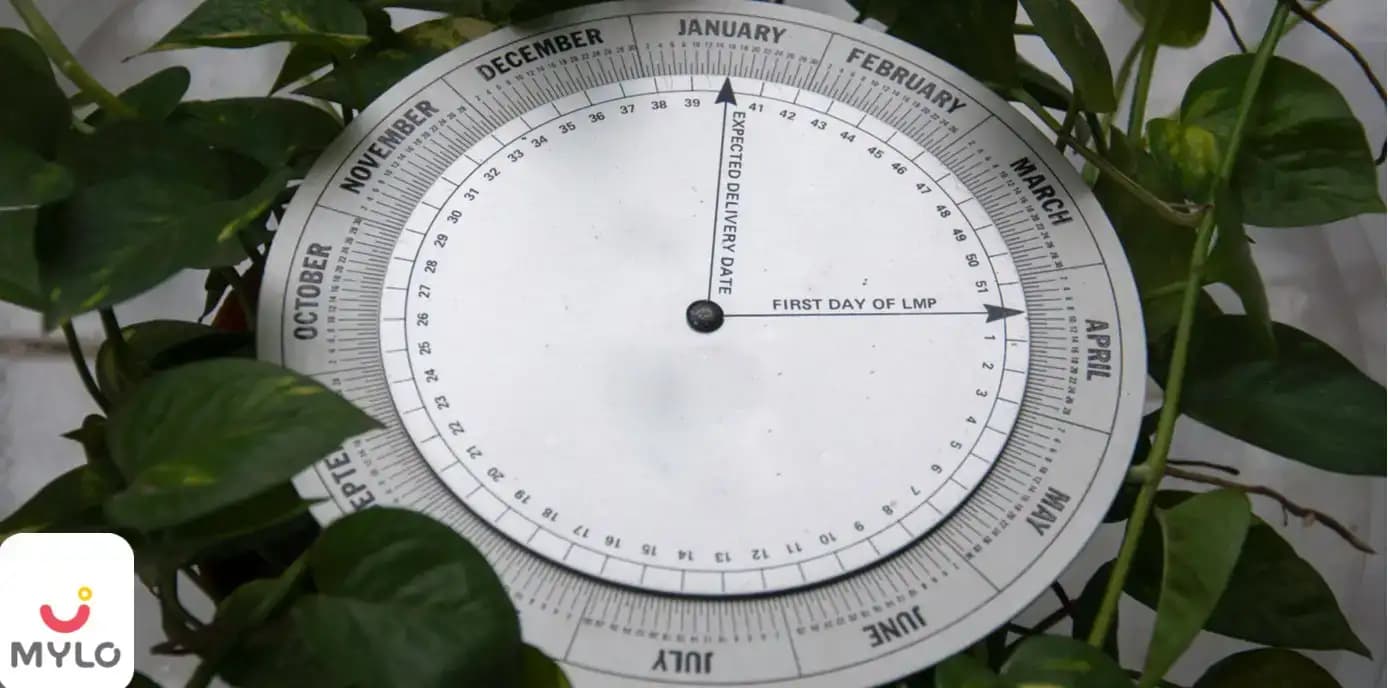

How to Determine Pregnancy Due Date with Irregular Periods?